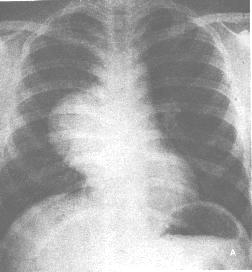

④充氣囊腫:此種囊腫極少見,有作者報告1 例為6 天男嬰,右胸腔內呈巨大薄壁充氣囊腫,肺尖及肋膈角可見受壓的肺組織,側位片見充氣囊腫向後下方突出、心影左移。術前診斷為“先天性肺囊腫”,手術及病理證實為胸內重複畸形,內含奶塊和綠色液體,與膈下十二指腸相通(圖1)。

食道重複畸形⑥音叉型食管:重複食管呈管狀與正常食管並行,下段匯合相通。可合併食管裂孔疝,反流性食管炎和食管狹窄。縱隔無包塊影。部分病例X 線片上顯示有椎體畸形(椎管裂、半椎體多見),肺不發育、食管閉鎖、腹內重複畸形等,對診斷意義很大。